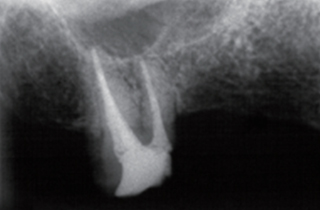

신경치료 후 남아있는 치질이 너무 짧거나 부족한 경우

크라운을 씌우기 전 치아안쪽에 기둥을 세우고 보강해주는 과정이 필요합니다.

포스트의 종류는 두가지가 있는데 사진은 기공소에서 맞춤형으로 제작된 포스트입니다.